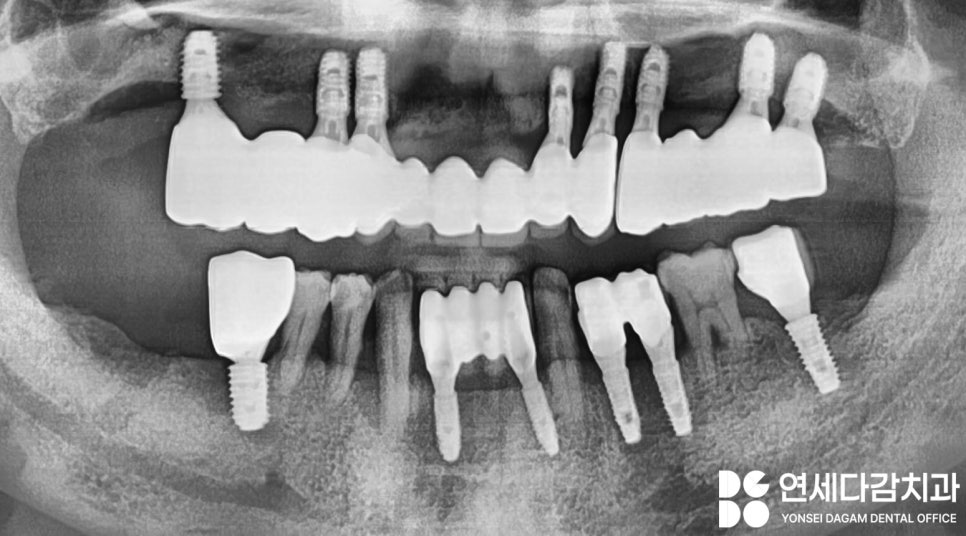

4개월 뒤 뼈의 재건과

픽스처와의 유착이

제대로 이루어지면

크라운이 올라가기 위한

단계를 진행합니다.

전체 임플란트 보철 제작 시

환자의 연하 작용, 안모, 발음 등을

종합적으로 평가하는 것이 중요합니다.

골흡수로 인한 안모 변화,

특히 수직 고경의 감소는

입술 주변의 주름 증가를 만듭니다.

따라서 가락시장역 치과 에서는

수직 고경을 높여

회복하는 것을 목표로 하였습니다.

이렇게 완성된 보철을

적응하기 위해서 충분히

사용해 보며 조정을 해나갔습니다.

다행히 빠르게 적응되어

최종적으로 접착하여

마무리하였는데요.